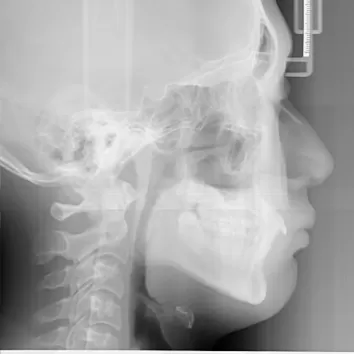

X-rays before treatment

[Panoramic Radiography/Lateral Cephalogram]